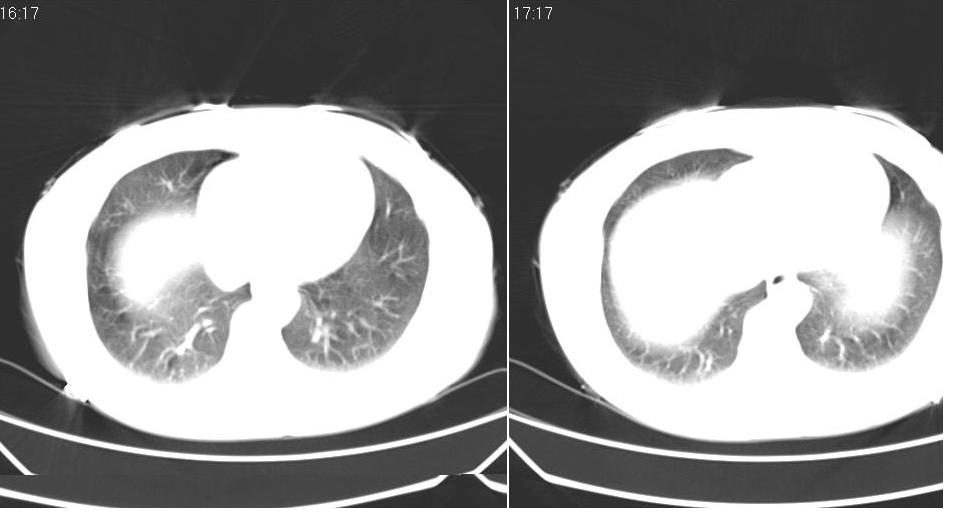

女 40岁,胸片体检发现右肺肿块,无任何症状。

下叶背段多发性小腺泡结节,考虑结核。

考虑右肺下叶背段继发性肺结核。